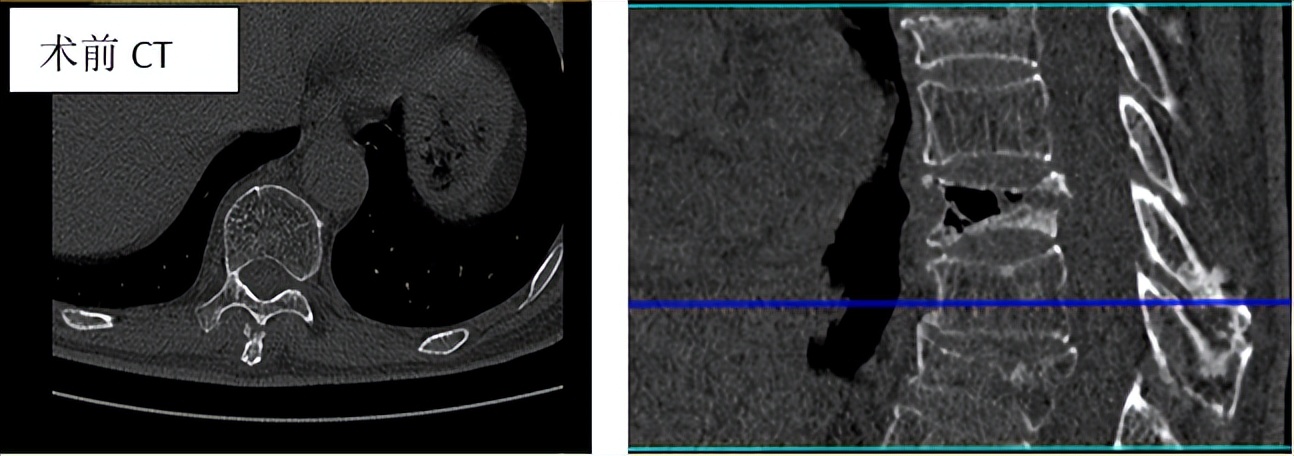

影像学检查

常用的有X线、CT、MRI、骨扫描。